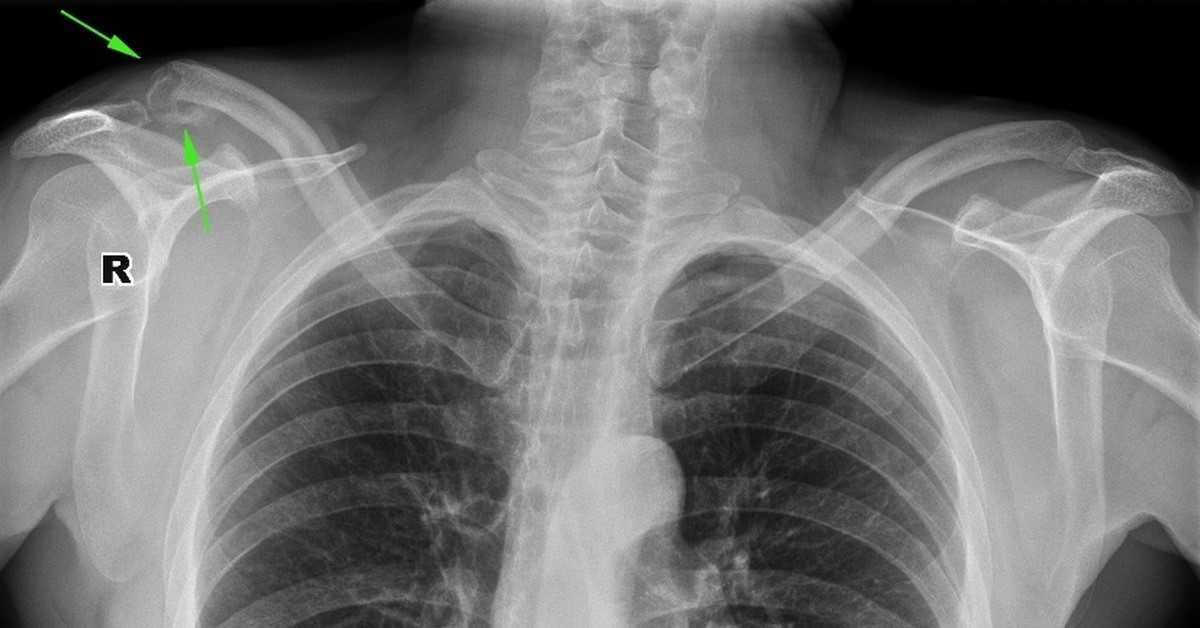

Изучение дозы излучения при рентгеновских исследованиях: визуализация